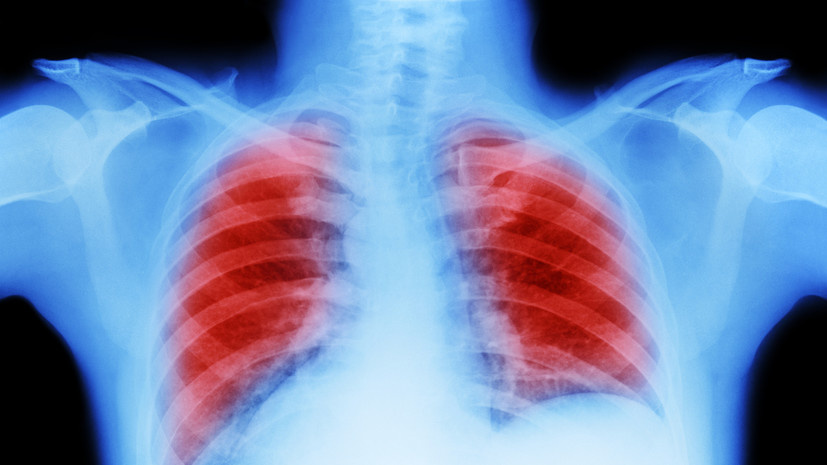

Профессор Лактионов рассказал о факторах развития рака лёгкого

Доктор медицинских наук, профессор первый заместитель директора НМИЦ онкологии имени Блохина Константин Лактионов рассказал о факторах развития рака лёгкого. «Курение, в принципе, вызывает достаточно широкий спектр нежелательных событий — сердечно-сосудистые заболевания, заболевания бронхолёгочной системы. Но для того, чтобы развилась локальная опухоль, стаж курения должен составлять 15—20 лет из расчёта пачки сигарет в день», — заявил он в беседе с газетой «Известия». По его словам, вред от вейпов и электронных сигарет может быть ниже, но он всё равно есть. Лактионов отметил, что вред для здоровья есть и от пассивного курения, но он не сопоставим с активным. Ранее, как сообщало «Радио 1», главный внештатный специалист психиатр-нарколог Минздрава Московской области Виталий Холдин рассказал о причинах «инсульта молодых».